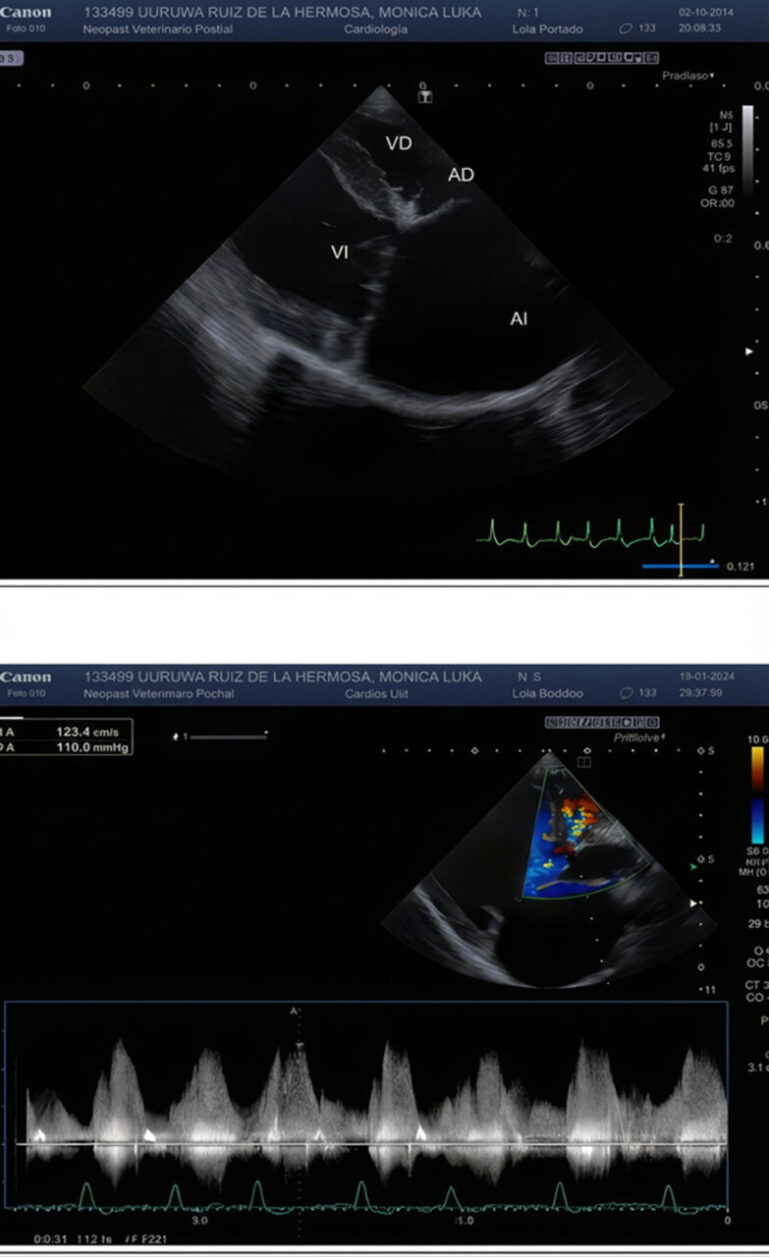

Antes de la planificación de la cirugía, se recomendó una revisión por parte del Servicio de Cardiología del centro para evaluar la gravedad de la patología cardiaca. Se realizó un estudio ecocardiográfico, que mostró la existencia de un defecto perimembranoso del septo interventricular y cuadricuspidía aórtica con grave remodelación atrioventricular izquierda y complicada con fibrilación atrial (FA) (imágenes 1 y 2). Se decidió mantener el tratamiento actual, con la excepción de la amiodarona, que se suspendió y sustituyó por diltiazem cada 12 horas y digoxina cada 12 horas para el tratamiento de la FA. También se añadió amlodipino cada 12 horas.